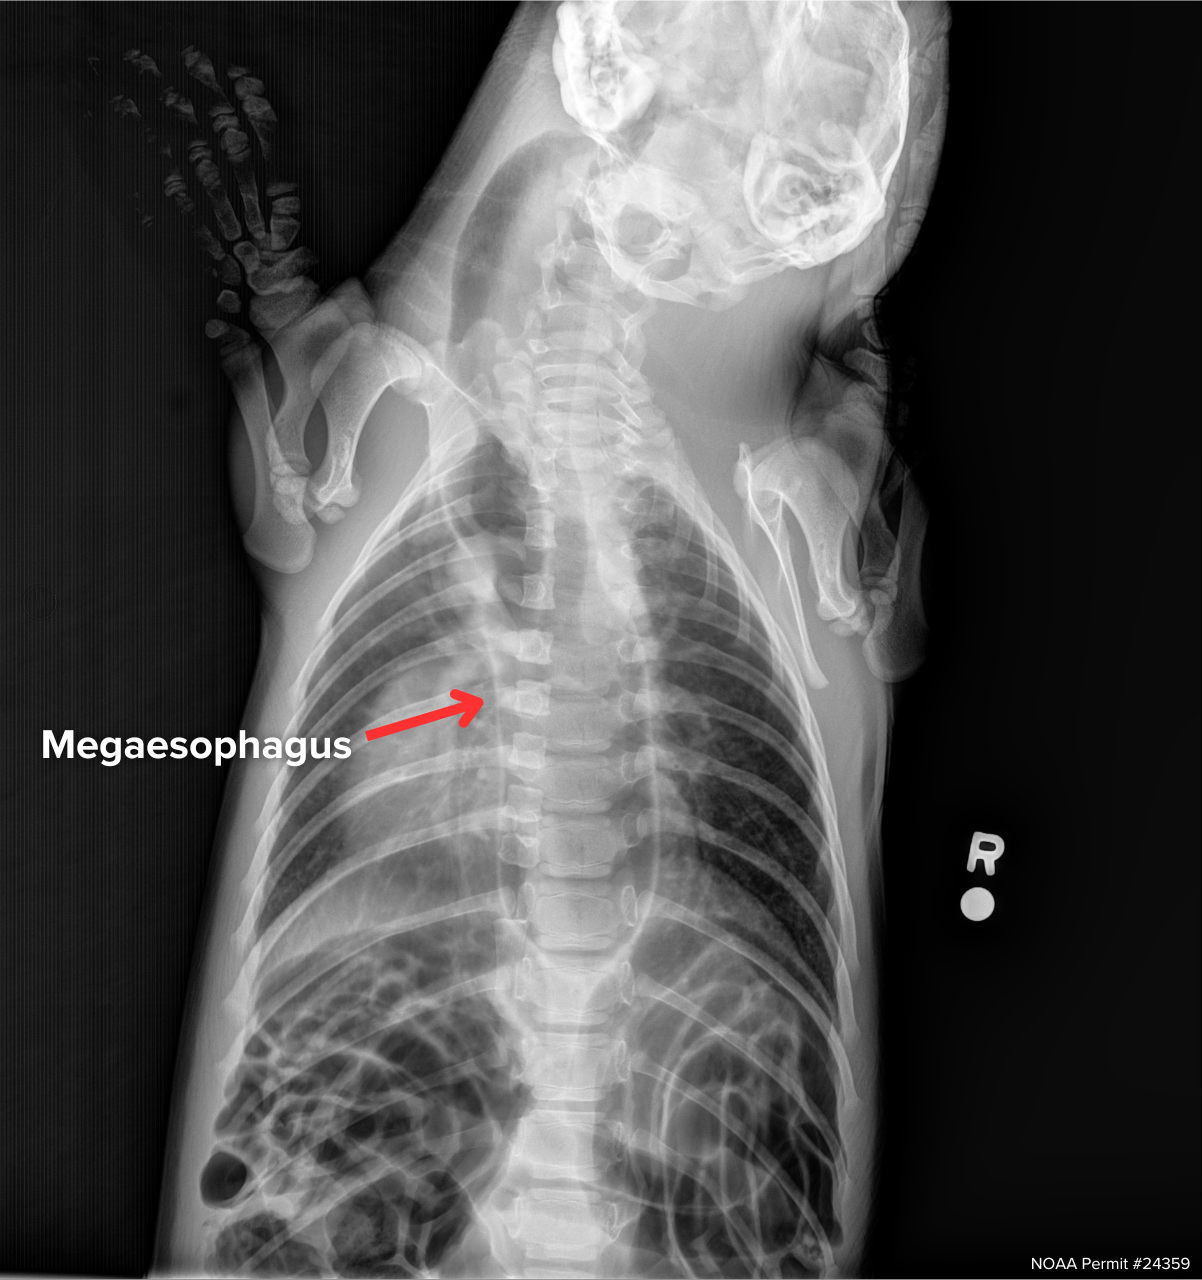

On June 3rd, he was given another examination, this time with x-rays as one of the added procedures, and the images that came back were not promising. Griffin had a condition called megaesophagus.

An x-ray of Griffin from June, with the red arrow pointing to his enlarged esophagus visible through his ribs and spine.

Megaesophagus is a disorder in which the esophagus (the tube between the mouth and the stomach) dilates and loses its ability to move food. This condition is not well-studied in seals, and its cause in these animals remains unclear. Symptoms include regurgitation, bloating, and sometimes secondary aspiration pneumonia. For domesticated dogs, there is a specialized chair to sit in after a feed that keeps the esophagus vertical, which helps gravity push the food down past the enlarged esophagus and into the stomach. This mechanism is something we have used with seal patients, but it is not a long-term solution. Historically, seals with megaesophagus would not be able to survive in the wild, nor be a candidate for relocation to a zoo or aquarium, and SR3 humanely euthanized them due to a lack of treatment options.

An x-ray of Griffin from October, with the red arrow pointing to his resolved esophagus.

“Fortunately, with continued supportive care, Griffin's bloating resolved and he was able to swim and forage like a normal seal," said Michelle. At the beginning of October, when he reached his release weight of 50 pounds, he was imaged a second time, and it was confirmed that Griffin’s esophagus had returned to a normal size.